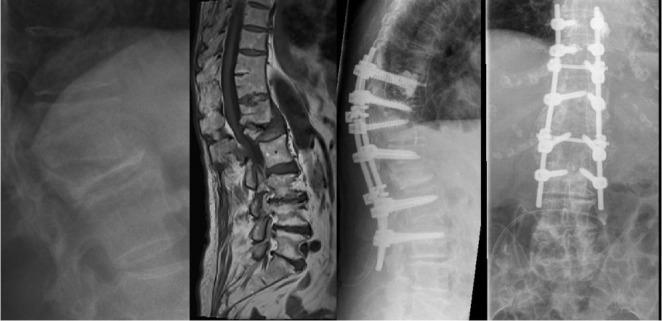

Specific and non-specific infections of the spine are rare. Due to their potential for severe instabilities, deformities and the impairment of neurological structures, the treatment is often prolonged and needs an interdisciplinary management. The clinical presentation is uncharacteristic, therefore diagnosis is often delayed. There are no prospective randomized studies for therapy recommendation. The surgical concept includes eradication of the infection and the reliable stabilization of involved segments. This concept is successful in most cases of endogenous vertebral osteomyelitis. The therapy of the exogenous spine infections after macro and micro surgery is more difficult, due to the critical wound situation and the involvement of the posterior parts of the spine. In these cases, infection-associated instability of the anterior part is complicated by critical posterior wound conditions. We present three cases of severe exogenous vertebral infections, where temporary external transpedicular spine fixation was used for salvage procedure, till soft tissue conditions have permitted a definitive internal stabilization.

脊柱的特异性和非特异性感染较为罕见。由于它们可能导致严重的不稳定、畸形以及神经结构受损,治疗往往较为漫长,且需要多学科管理。临床表现不典型,因此诊断常常延迟。目前尚无用于推荐治疗方法的前瞻性随机研究。手术理念包括根除感染以及对受累节段进行可靠的稳定固定。这一理念在大多数内源性椎体骨髓炎病例中取得了成功。由于伤口情况危急以及脊柱后部受累,宏观和微观手术后外源性脊柱感染的治疗更为困难。在这些病例中,前部感染相关的不稳定因后部伤口情况危急而变得复杂。我们展示了三例严重的外源性椎体感染病例,其中采用了临时经椎弓根外固定脊柱进行挽救手术,直至软组织条件允许进行最终的内固定。